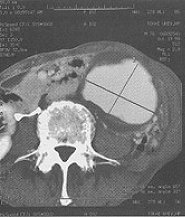

腹部のCTは図❷のとおりで、大きな大動脈瘤があり、心血管外科に依頼した。破裂する危険があるので至急手術をしますとの返事。この説明に、患者さんは立派な人物で、「重要な病気をみつけていただき、ありがとうございました」と礼を言われた。小出教授の執刀で人工血管置換の大手術が行われた。術後の経過はきわめてよく、1ヵ月後には口腔外科の病棟に転棟し、顎骨の腫瘍の手術をした。病理診断は歯原性嚢胞であった。